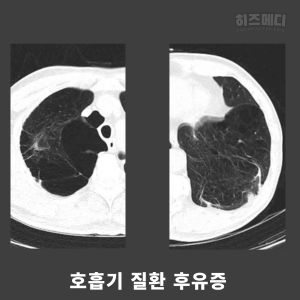

9) 호흡기 질환 후유증

폐렴이나 결핵 같은 호흡기 질환을 앓고 나면, 그 후유증으로 폐가 딱딱해지거나, 흉막에 염증이 남을 수 있습니다. 이런 후유증으로 인해 폐의 확장이 제한될 수 있습니다.